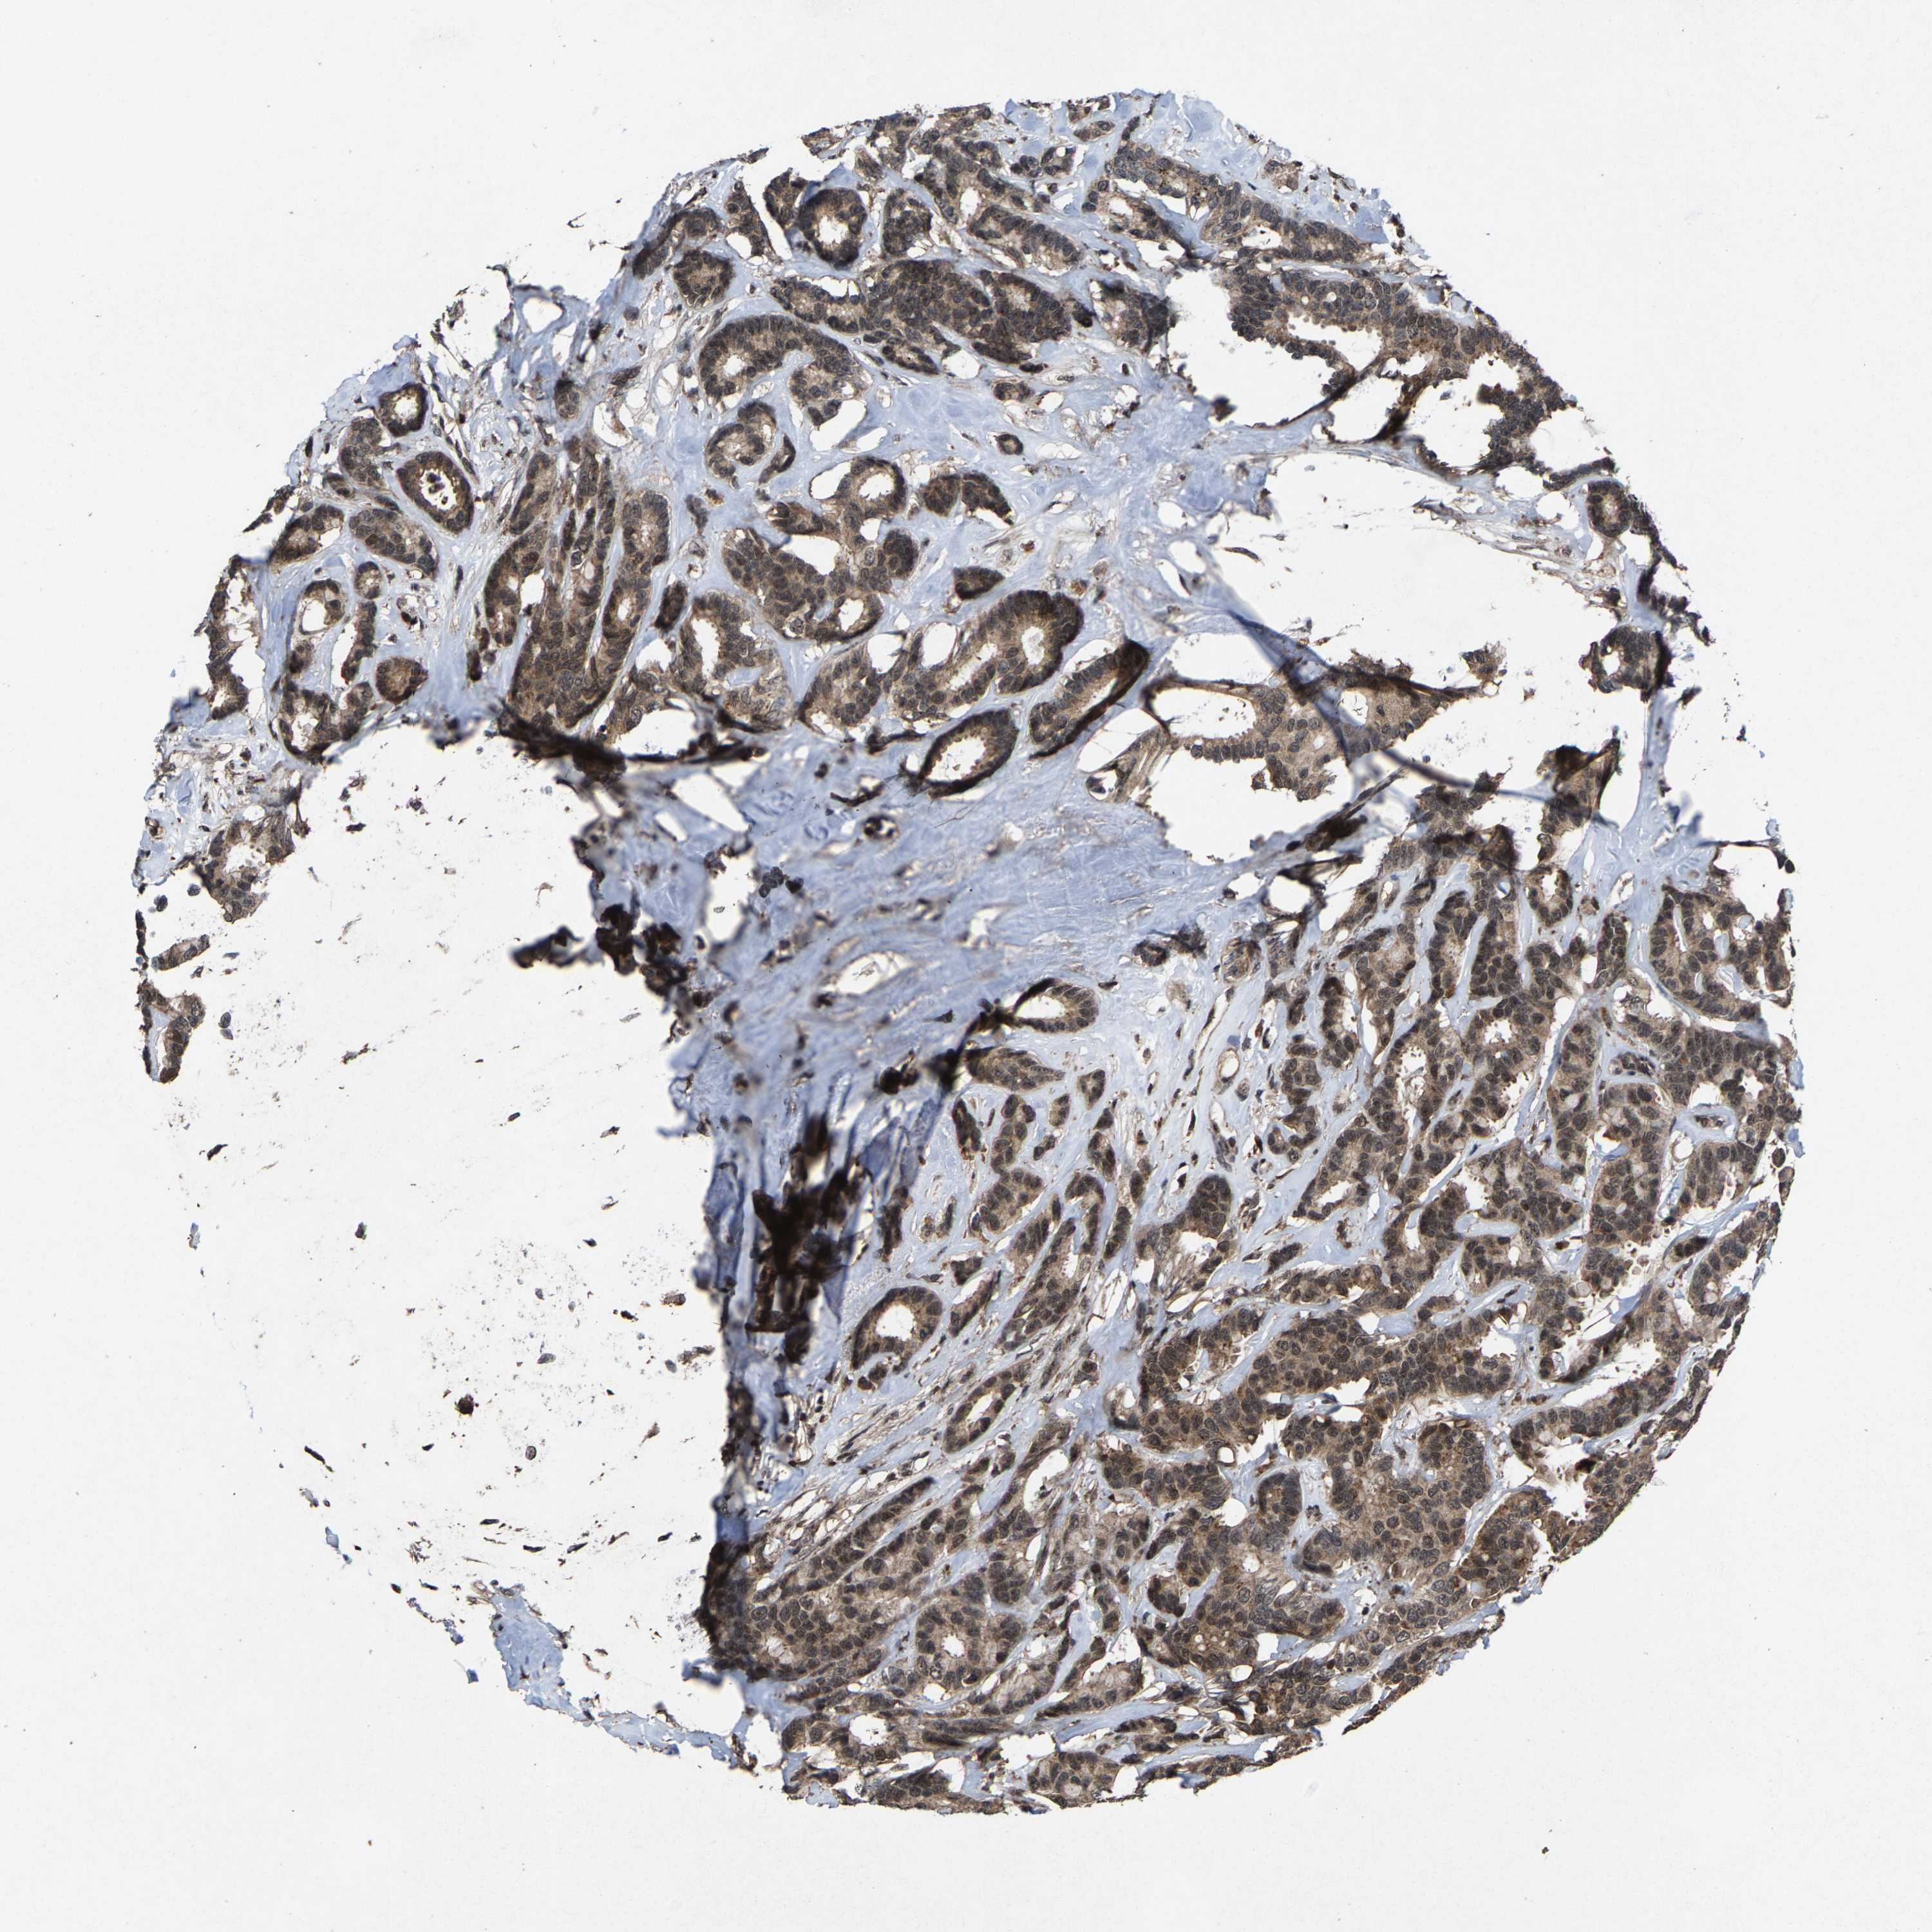

CANCER BREAST CANCER Show tissue menu

BRCA TCGA BRCA VALIDATION PROTEIN EXPRESSION